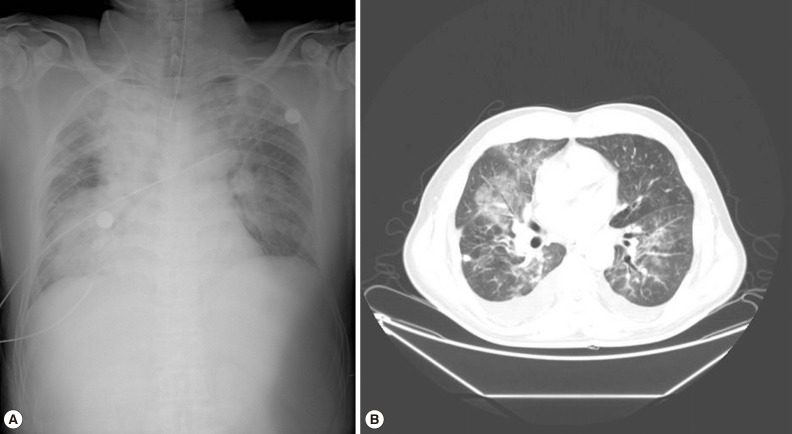

On admission, his body temperature was 37.3℃, blood pressure was 109/65 mmHg, and pulse rate was 180 beats per min. He exhibited a drowsy mental status and irritability. While the patient was maintained on a continuous mandatory ventilation (CMV) mode with tidal volume of 450 ml, respiration rate of 20/min, FiO2 of 0.8, and positive end-expiratory pressure (PEEP) of 15 cmH2O, arterial blood gas analysis (ABGA) revealed the following findings: pH, 7.22; PaCO2, 36.3 mmHg; PaO2, 101 mmHg; HCO3, 14.4 mmol/L; and O2 saturation, 95.7%. Central venous pressure determined from the right jugular central venous catheter was 10 cmH2O. His hemoglobin level was 11.1 g/dl, hematocrit was 33.6%, WBC count was 9,910/µl, and platelet count was 37,000/µl. Serum blood urea nitrogen (BUN) and creatinine levels were 38.1 mg/dl and 1.35 mg/dl, respectively. Total and direct bilirubin levels were 9.3 mg/L and 7.8 mg/L, respectively; aspartate aminotransferase, 183 IU/L; alanine aminotransferase, 115 IU/L; and alkaline phosphatase, 423 IU/L. Other laboratory tests revealed glucose, 161 mg/dl; C-reactive protein, 210.1 mg/L; lactic acid, 2.8 mmol/L; activated partial thromboplastin time, 48.9 sec; prothrombin time, 18.9 sec; and D-dimer, 14.20 µg/ml. A test for anti-HIV antibody was negative. The levels of muscle enzymes for detection of myocardial infarction were normal, and an electrocardiogram showed sinus tachycardia and there was no evidence of myocardial ischemia. A chest radiograph (Fig. 1A) and a chest CT scan (Fig. 1B) revealed haziness in both lungs. The malaria rapid antigen test (SD Bioline Ag P.f/pan Rapid) (SD BIOLINE, Seoul, Korea) was performed; the test was positive for P. vivax but negative for P. falciparum.